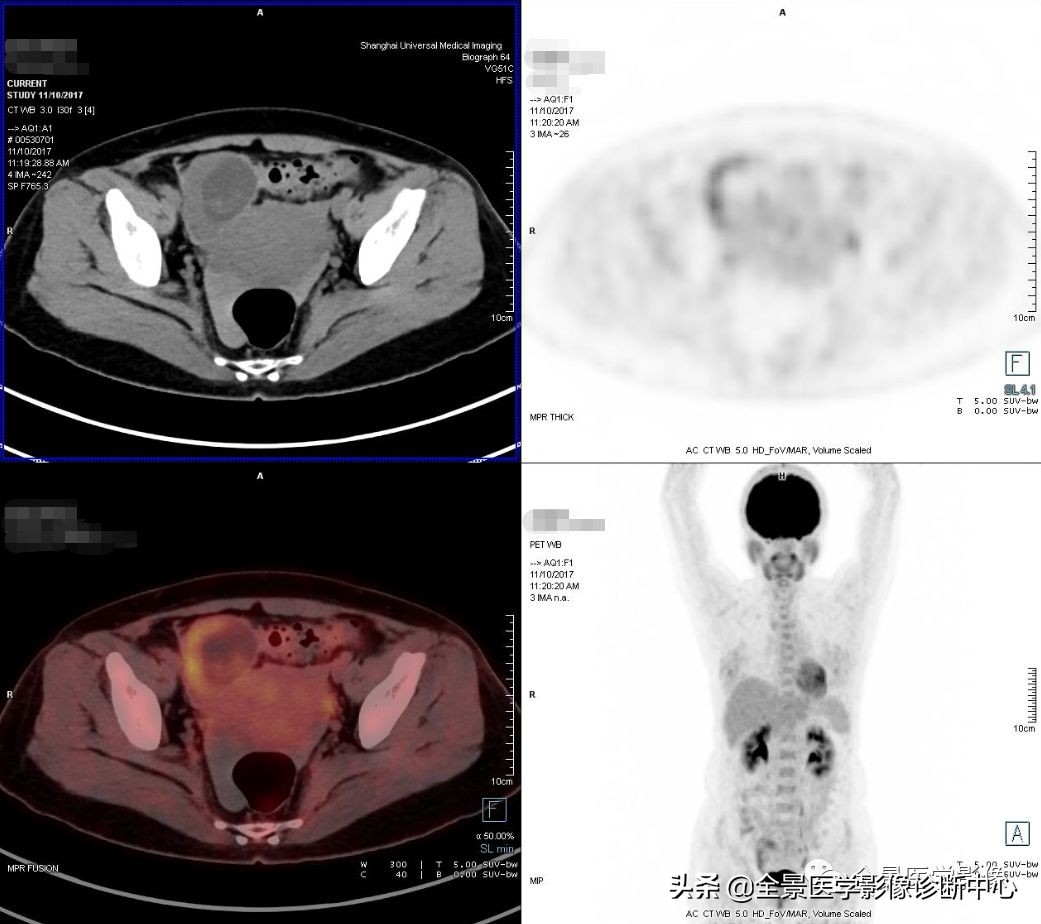

全景PET/CT诊断组李医生在开始为她进行阅片中发现其右侧附件区长了一个长径约8cm的囊实性奇怪病灶,病灶呈椭圆形,与脑海中浮现的所有附件常见病灶都不太相像。

即请全景医学影像石华铮主任会诊,坐定没一会儿,石主任倒吸了一口凉气说:这是发生于右侧输卵管的宫外孕呀,更为严峻的是:病人的宫外孕已经破裂伴有活动性出血(盆腔内子宫直肠陷凹出现较多游离高密度液体影)

也就是说检查者的腹腔内正在持续出血而自己竟然还不知情……遂立刻启动全景危急重病患处理预案,并为慎重起见,马上让杨春山教授再次复核影像诊断结果并获得支持,报备医务处,填报危急值表。